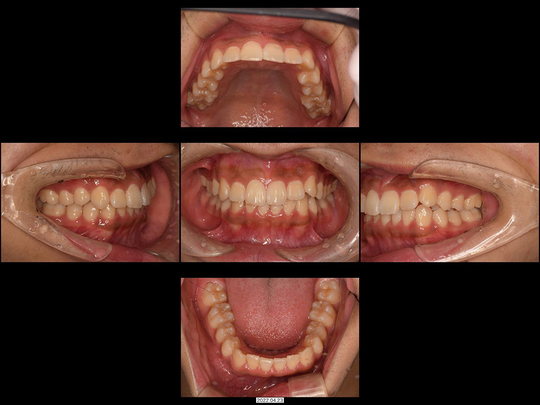

Mさん 10代 女性

矯正前

画像をクリックで拡大

矯正後

治療の説明

マウスピース型矯正装置を使った矯正治療にて全体矯正しました。抜歯することなく治療を終えています。

治療の期間・回数

1年8か月、12回

​費用

877,800円